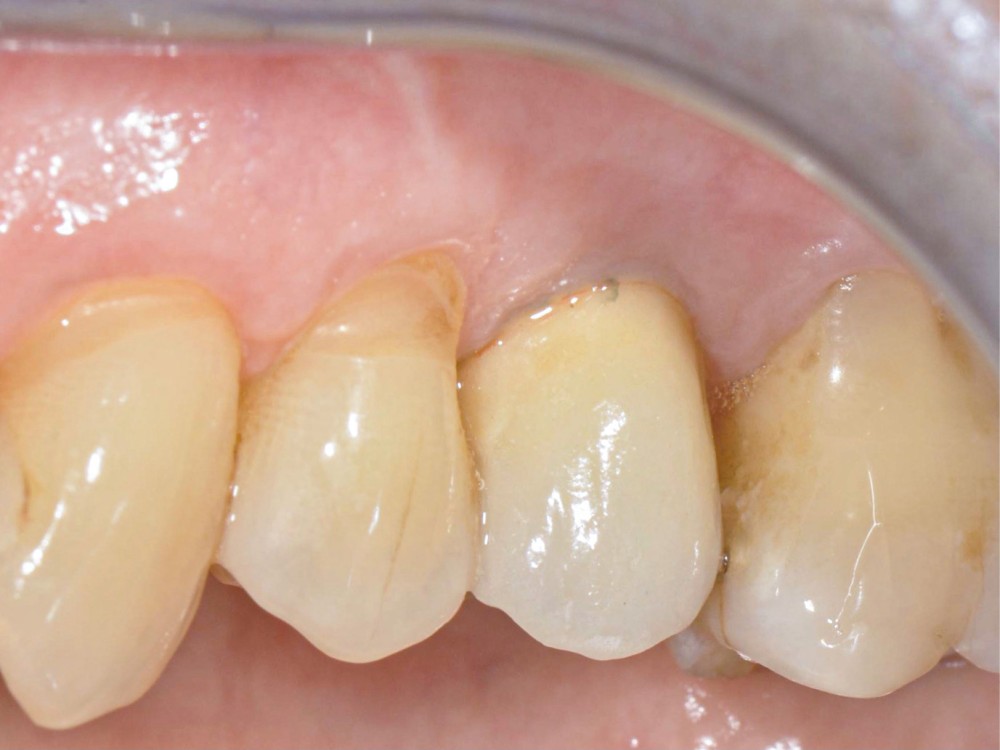

13 et 14. À 3 ans, une régénération osseuse satisfaisante et un bel aspect des tissus péri-implantaires sont observés. Les poches font 3 mm en mésial, distal et palatin, et 2 mm en vestibulaire. Il n’y a pas de saignement au sondage.